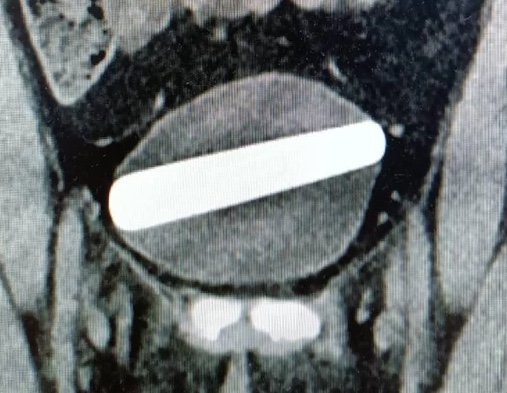

Vibrador de cristal Foto: Shaare Zedek Medical Center / Divulgação

Exames de imagem mostraram que depois de passar pela uretra, o objeto acabou se posicionando na horizontal na bexiga.